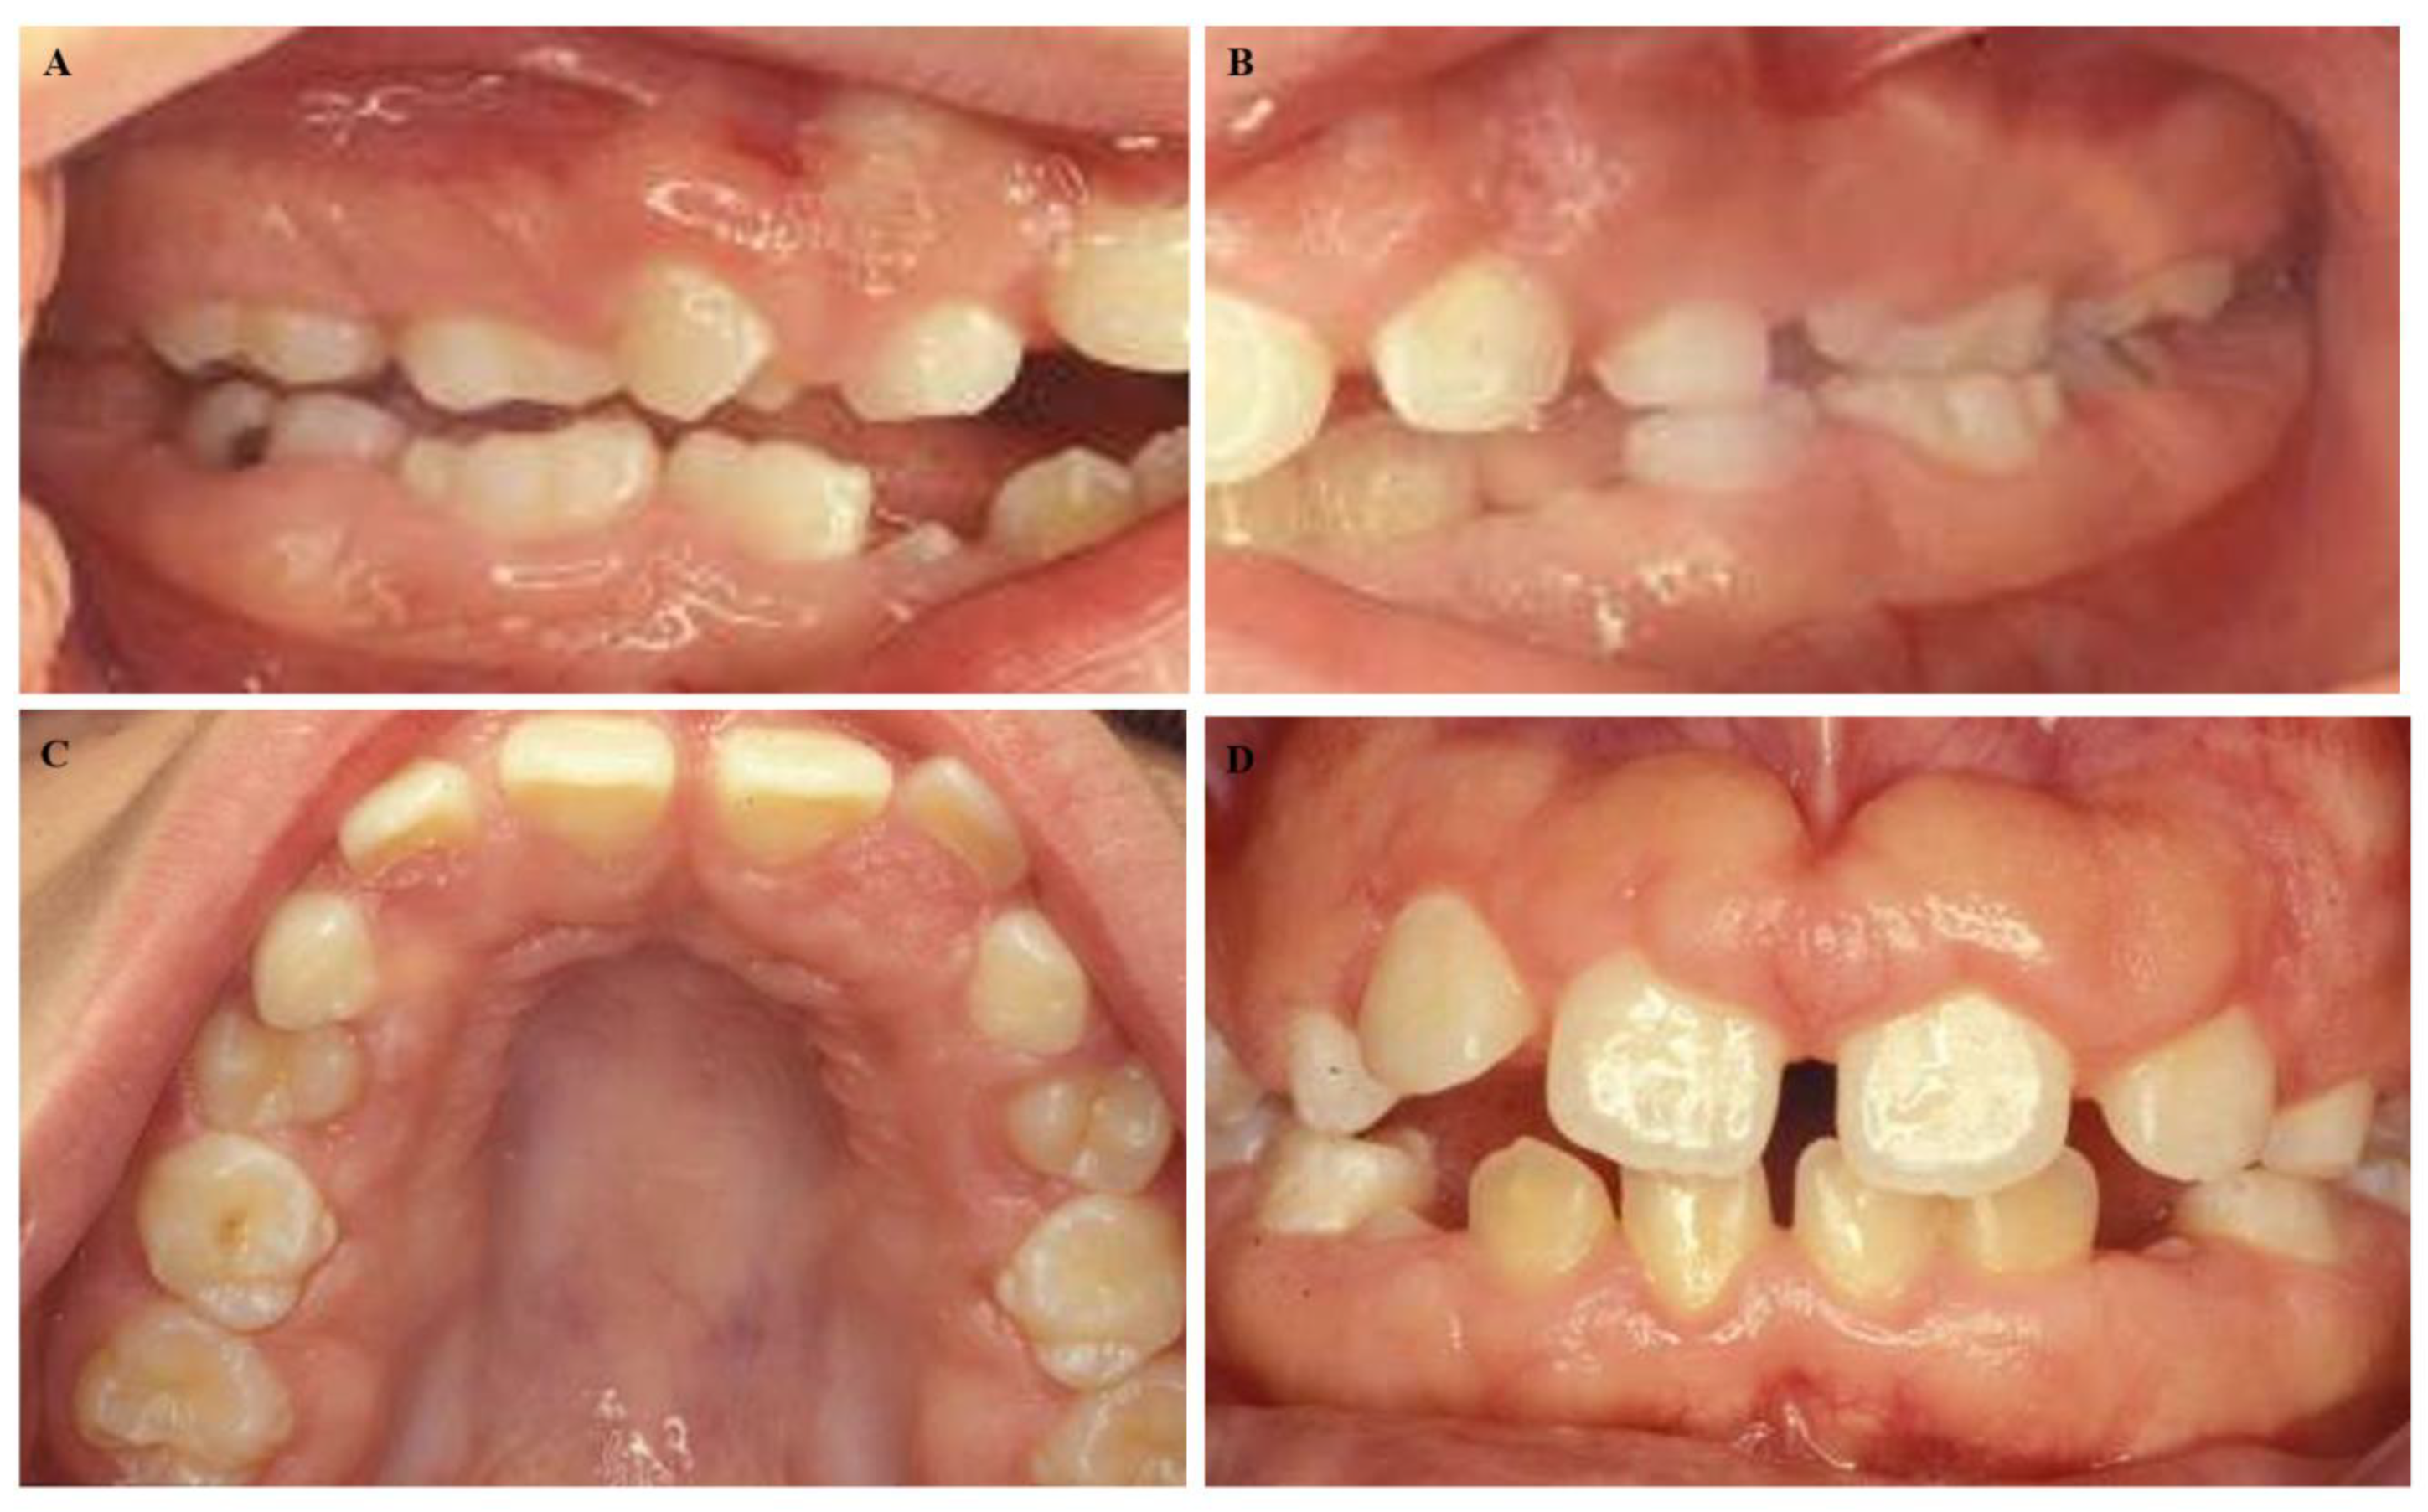

A 50-year-old male presented at the Dental School, University of Seville, with a chief complaint of “gingival swelling all over his mouth”. After the completion of the informed consent, the cases were studied. The swelling caused difficulties in speaking and chewing. No other complaints including pain, bleeding, or halitosis were present. The patient began 4–5 years ago and progressed slowly. His medical history was unremarkable, and he was not taking any medication. His weight and height were within normal limits. An extraoral examination revealed a natural face. The patient could close his lips; however, he was an oral breather. An intraoral examination presented signs of gingival enlargement, a bilateral fullness of the cheeks with painless swelling and palate extension to the midline (Figure 1A–D). We suggested an examination of his family. His wife suffered chronic periodontitis without any gingival enlargement. He had two daughters: one ten years old and the other twelve years old. The younger daughter presented with regular aspects of the gums and the oldest daughter presented with generalized enlargement similar to her father (Figure 2A–D). According to these data, a diagnosis of hereditary gingival fibromatosis was established. The treatment consisted of a rigorous oral hygiene program in addition to professional debridement and gingivectomy at both maxillary quadrants.

Figure 2.

Intraoral images of the 12-year-old female daughter of the male patient in Figure 1. (A–C) We observed mixed dentition, (D) with malocclusion similar to her father, including an anterior open bite and delayed eruption.